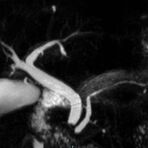

Aorta

• Bauchgefäße

• Erfassung und Verlaufskontrolle bei arteriellen Aneurysmen (Aussackungen der Arterien), vor allem der Bauchaorta

• Darstellung von Gefäßengen an Nierenarterien, Baucharterien und Becken-/Beinarterien

MR-Angiografie (MRA)

Angiographie ohne Kontrastmittel

• MR-Angiografie ohne Kontrastmittel

• Time of Flight (TOF)-Angiographie

• Phasenkontrastangiographie (PCA). Geeignet zur Quantifizierung Stenose-/Insuffizienzgrad z.B. bei Herzklappen, falls echokardiographisch die Untersuchungsbedingungen eingeschränkt sind.

Je nach Fragestellung und Körperregion Gefäßdarstellung ohne Kontrastmittel bei Kontrastmittelunverträglichkeit oder terminaler Niereninsuffizienz möglich.

Ganzkörper Angiographie mit Kontrastmittel

• MR-Angiographie mit Kontrastmittel

• Erfassung arterieller und venöser Gefäße/Bypässe aller Körperregionen mit 3D-Rekonstruktion

• je nach klinischer Fragestellung zeitaufgelöste MR-Angiographie (4D-MRA) z.B. bei Frage arteriovenöse Fistel/ Shunt oder Darstellung Unterschenkelarterien vor geplanter Bypassoperation.